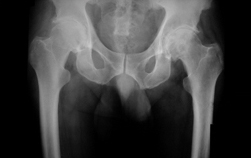

- 관절염으로 변형된 고관절 사진